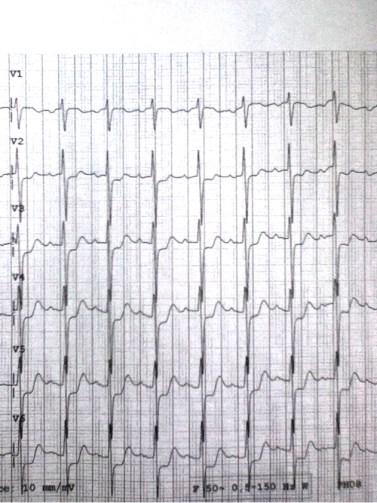

Precordial leads

His doctor said he had to do some other tests due to of EKG signs of LVH but my friend said I’m still not well so he called and sent me the photo of his EKG. 9.20 am.

I called my coll on duty that morning and told him: have you seen ST in aVR? He answered me a little fuzzy and said let’s wait for the Troponin. First sign of no respect . Here is the EKG in ED.